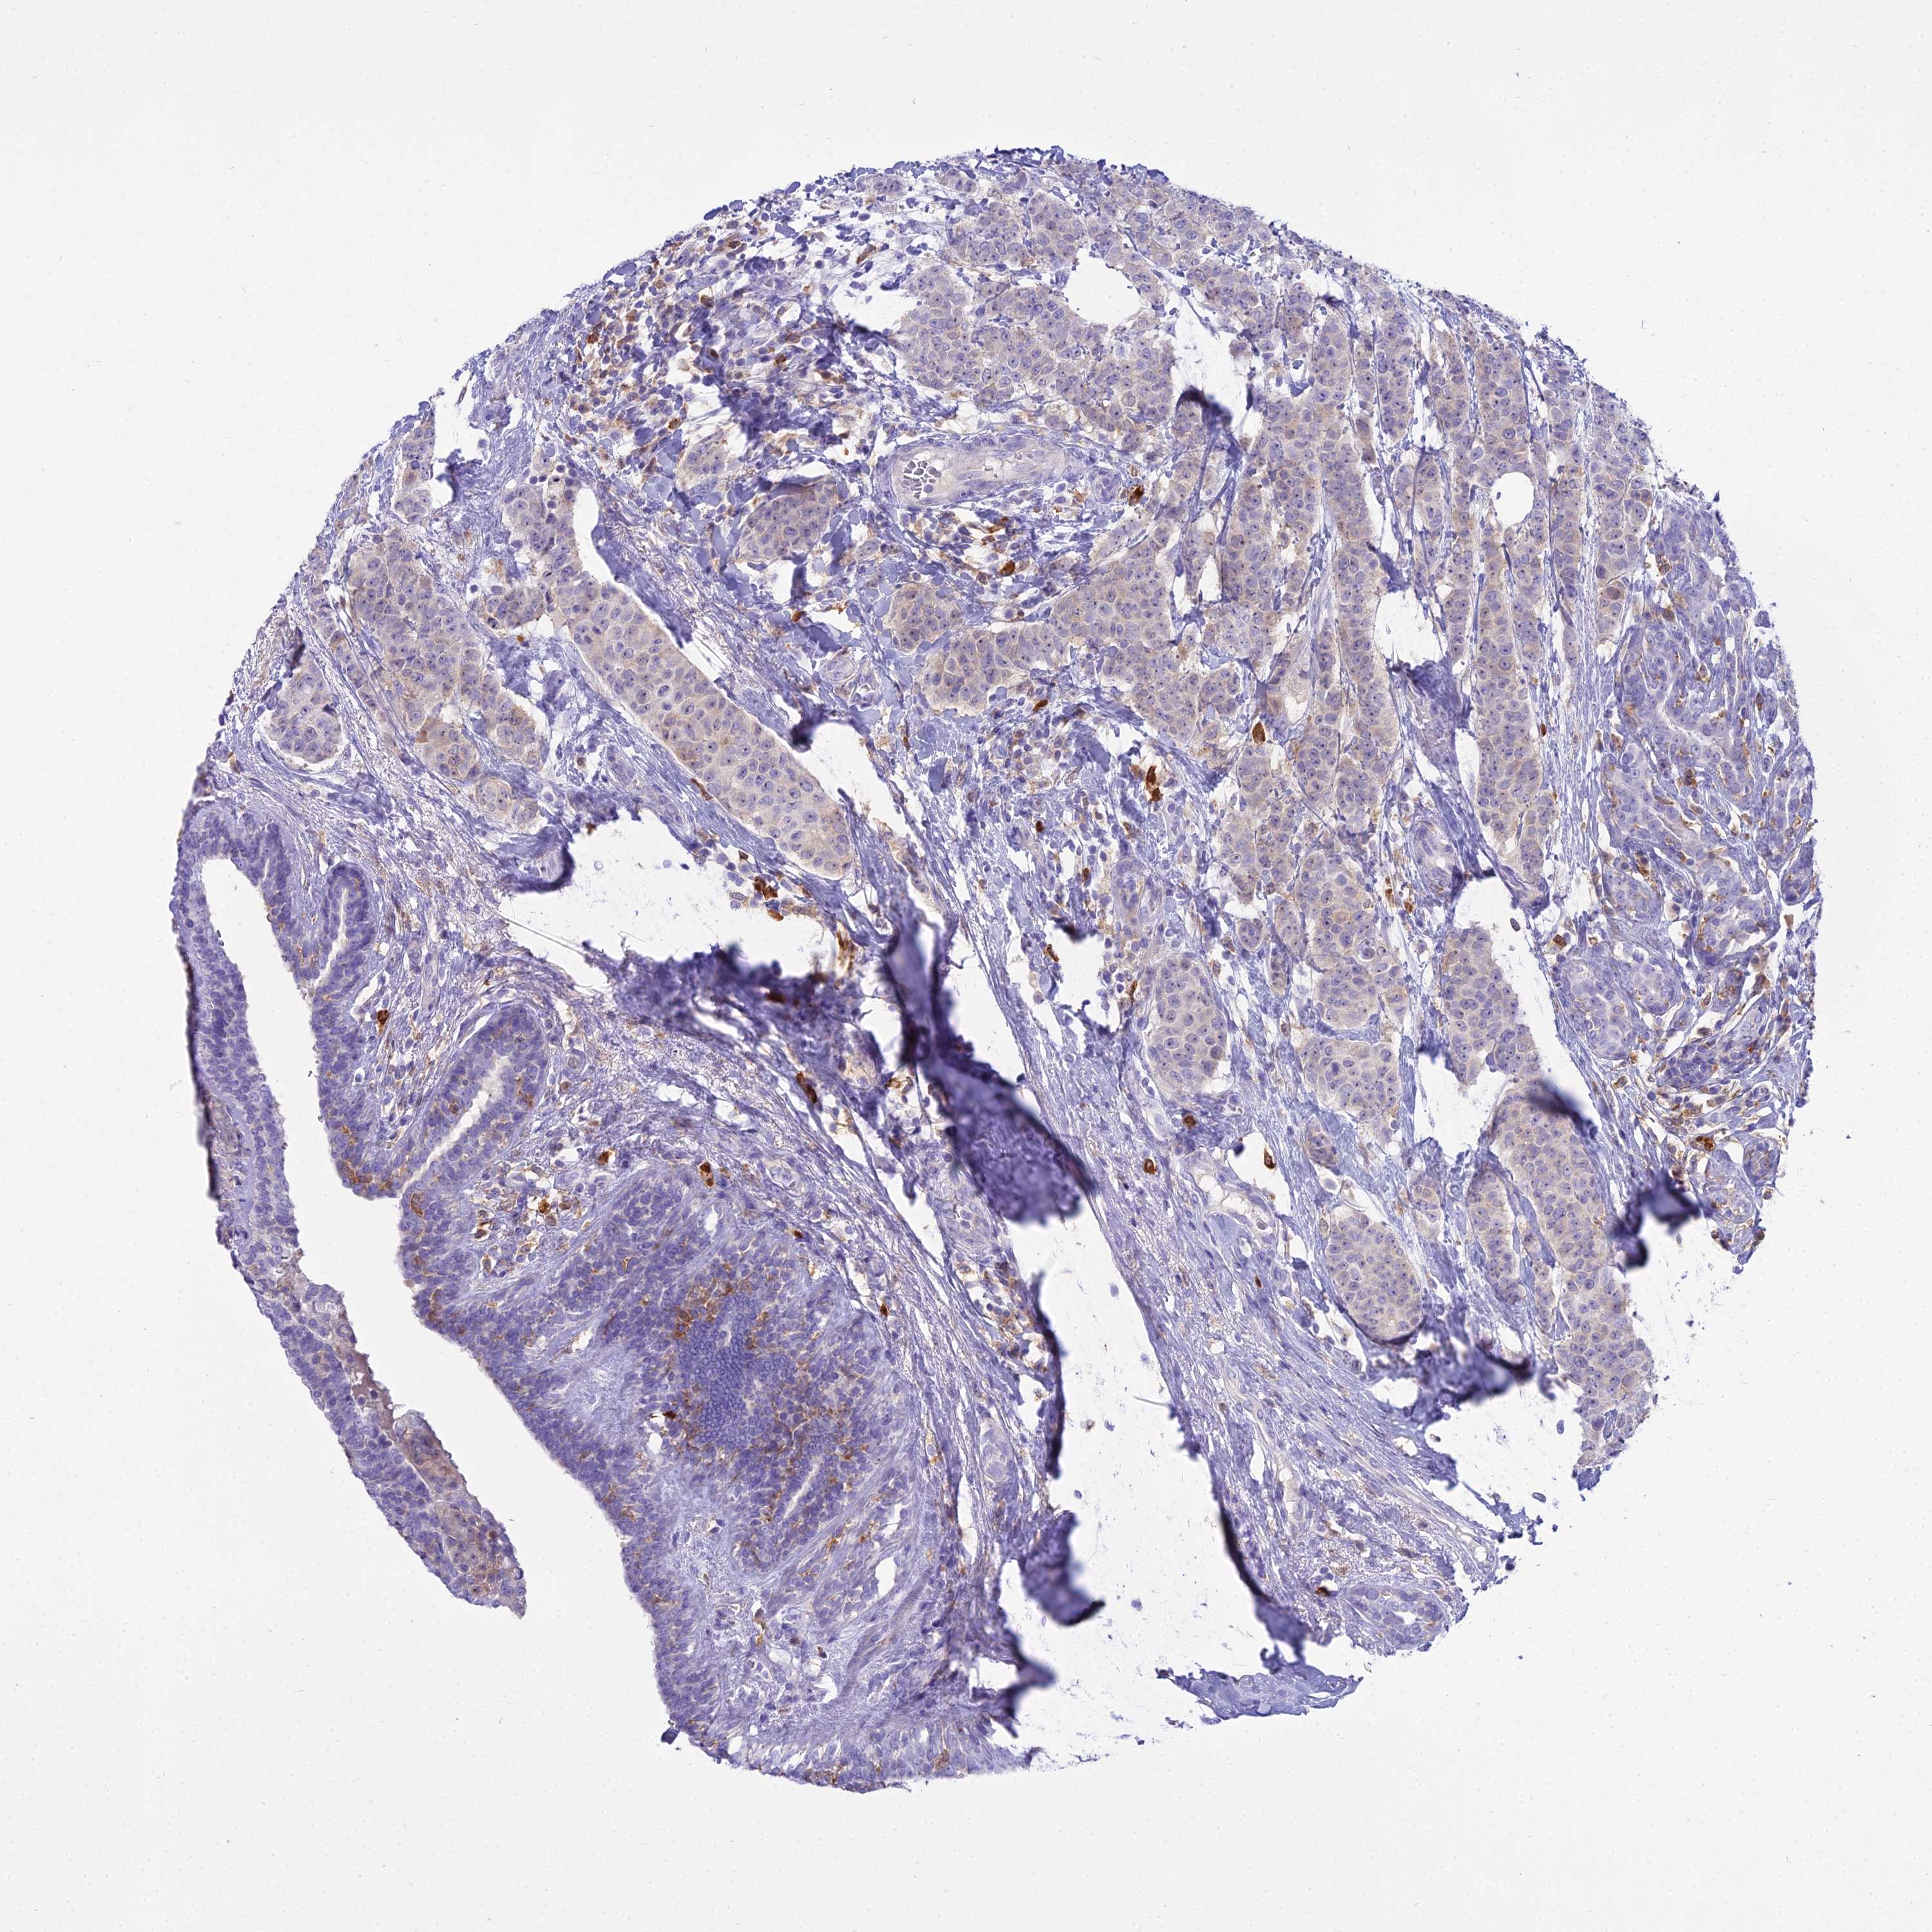

CANCER BREAST CANCER Show tissue menu

BRCA TCGA BRCA VALIDATION PROTEIN EXPRESSION